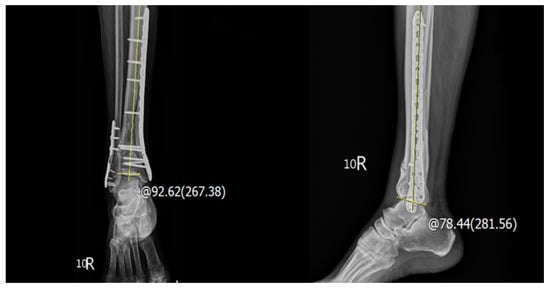

| LDTA, n (%) | - | - | - | 0.614 |

| ≤10° | 68 (85.0%) | 66 (86.8%) | 134 (85.9%) | |

| >10° | 12 (15.0%) | 10 (13.2%) | 22 (14.1%) | |

| ADTA, n (%) | - | - | - | 0.868 |

| ≤10° | 66 (82.5%) | 63 (82.9%) | 129 (82.7%) | |

| >10° | 14 (17.5%) | 13 (17.1%) | 27 (17.3%) | |